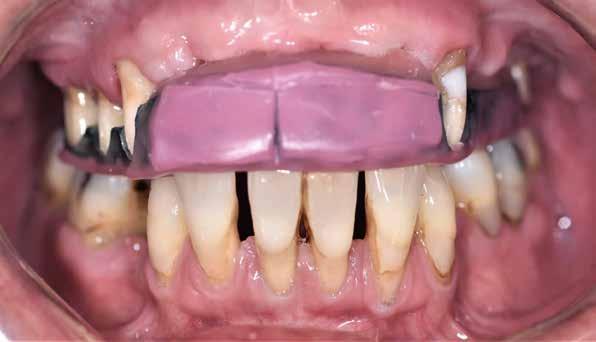

1–2. képek: Kiindulási helyzet.

3. kép: Új teleszkópos fogpótlás az 16, 15, 13, 23 és 27 fogakra.

Teleszkópos munka, élő eset bemutatásával ismertetem, mi az, ami már lehetséges. A munkaasztal-szkenneren kívül bevetésre került a digitális munkafolyamatok során egy intraorális szkenner (IOS) is. A 3D nyomtatású testek gyártása a laboratóriumban LCD- és DLP nyomtatókkal történt. A fémes komponenseket szelektív lézerolvasztásos (SLM) technológiával készíttettük.

Kiindulási helyzet

A páciens látlelete a következő:

• krónikus általános parodontitis

• a 24-től terjedő parodontális fekély

• hatástalan kapcsos felső fogpótlás (1-2. képek)